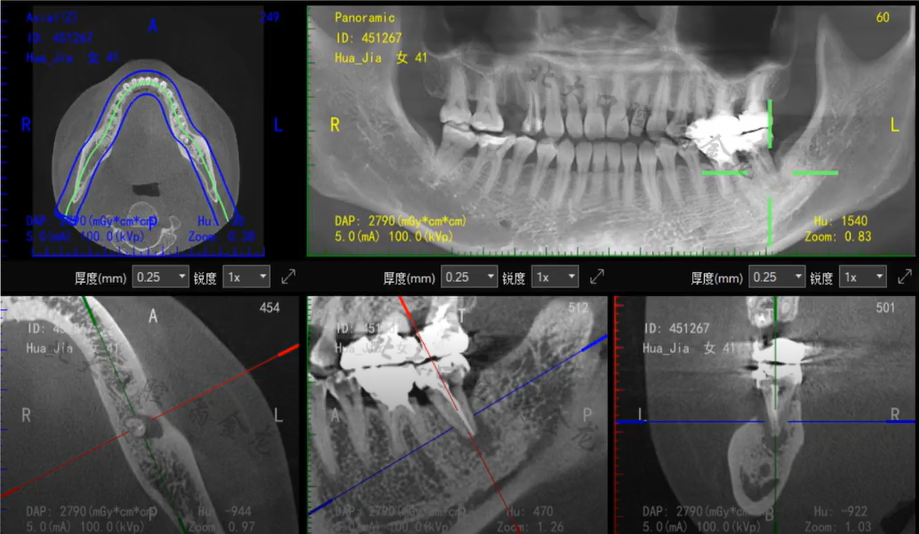

以下病例,您会考虑怎么做?

图片来源于训练营